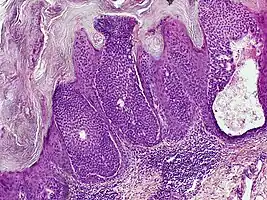

They are described as < 1 to 2 cm, pink/red shiny, exophytic lesions that can be pigmented and are clinically very similar to pyogenic granulomas.[3] Histologically, the cells as PAS-positive and clearly surrounded by normal keratinocytes. These tumors are surgically excised usually without complication or recurrence, although malignant porocarcinomas can recur and metastasize to local lymph nodes.[5]

Dermoscopy and histopathology of eccrine poroma: (A) Clinical presentation of a nonpigmented eccrine poroma sensu stricto as a pink nodule located on the foot (B,C) Dermoscopy shows milky red areas (light blue arrow), milky red globules (dark blue triangle), and dotted vessels (black arrow) (original magnifications ×20 and ×40, respectively). (D,E) Histopathologically, the neoplasm consists of poroid and cuticular cells and tubular structures that are continuous with the epidermis (H&E stain, original magnifications ×10 and ×40, respectively).[6]